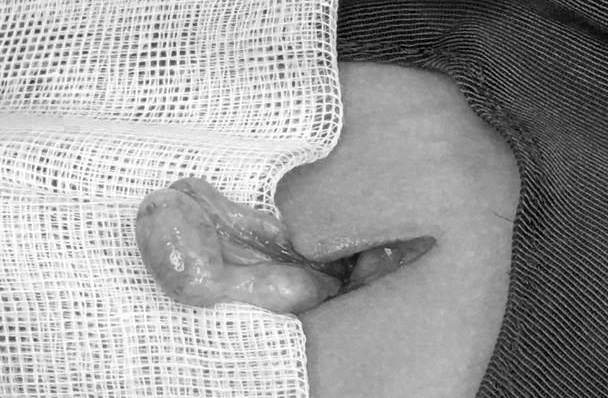

| Tinh hoàn lạc chỗ được đưa ra khỏi vị trí ống bẹn. (Ảnh: BVCC). |

Qua hội chẩn, các bác sĩ chẩn đoán bệnh nhân bị tinh hoàn trái lạc chỗ. Trong quá trình phẫu thuật hạ tinh hoàn lạc chỗ, các bác sĩ tiến hành giải phóng tinh hoàn trái khỏi tổ chức dây xơ ống bẹn và cố định dưới bìu cho trẻ.